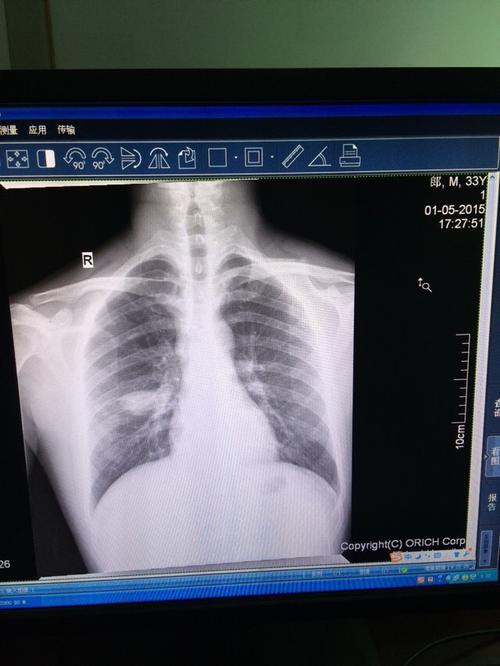

论坛各位便宜帮忙看我家人胸片是不是肿瘤?

看片诊病之典型急诊胸片分享

冯xx男51岁五官科诊咽炎,咳嗽行胸片常规检查,发现右下肺占位,ct同诊